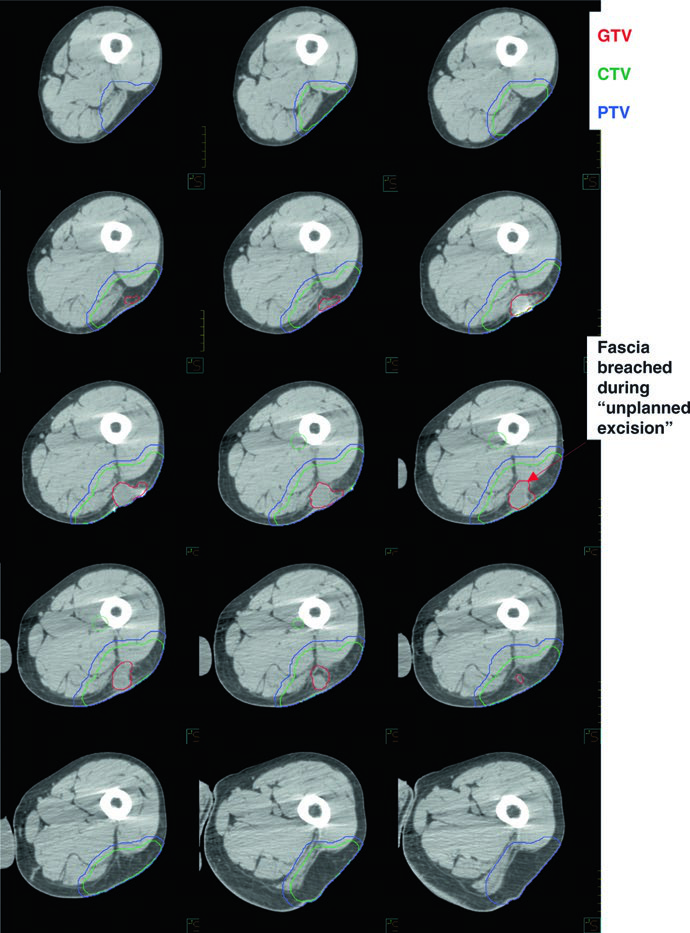

En casos de excisión no planificada (el llamado «error quirúrgico» con márgenes positivos), los márgenes deben ser generosos: el volumen debe incluir el GTV postoperatorio o cualquier GTV residual, todos los tejidos manipulados quirúrgicamente, la fascia violada, más 4 cm longitudinalmente y 1,5 cm radialmente hasta la barrera anatómica más cercana.

| CTV50 | GTV + margen de 4 cm longitudinal y 1,5 cm radial, limitado por barreras anatómicas (hueso, fascia). Edema peritumoral (T2-RM) contorneado por separado con margen de 1–2 cm. En excisiones no planificadas: GTVpostop + todos los tejidos manipulados + fascia violada + márgenes de 4 cm/1,5 cm. |